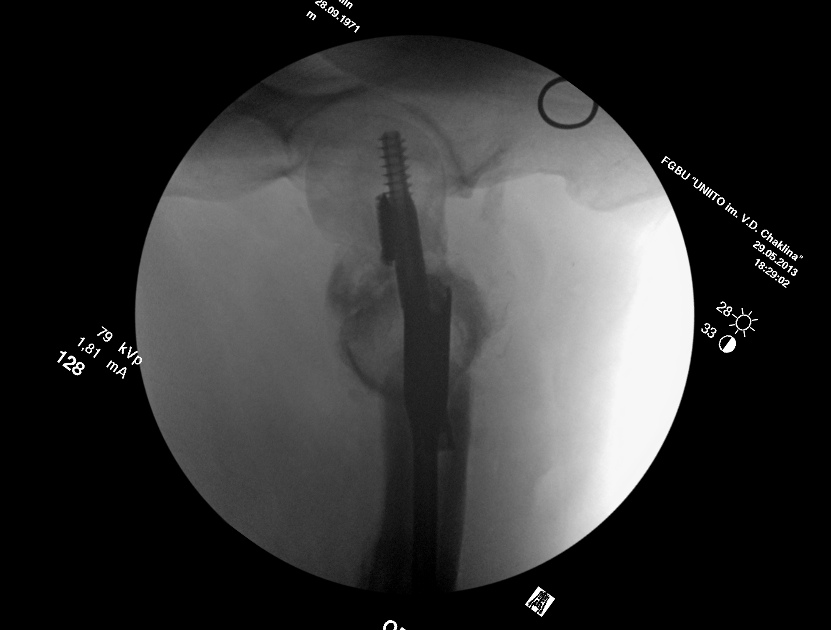

Насчет ревизионного штифтования - вот пример, вчера сделали.